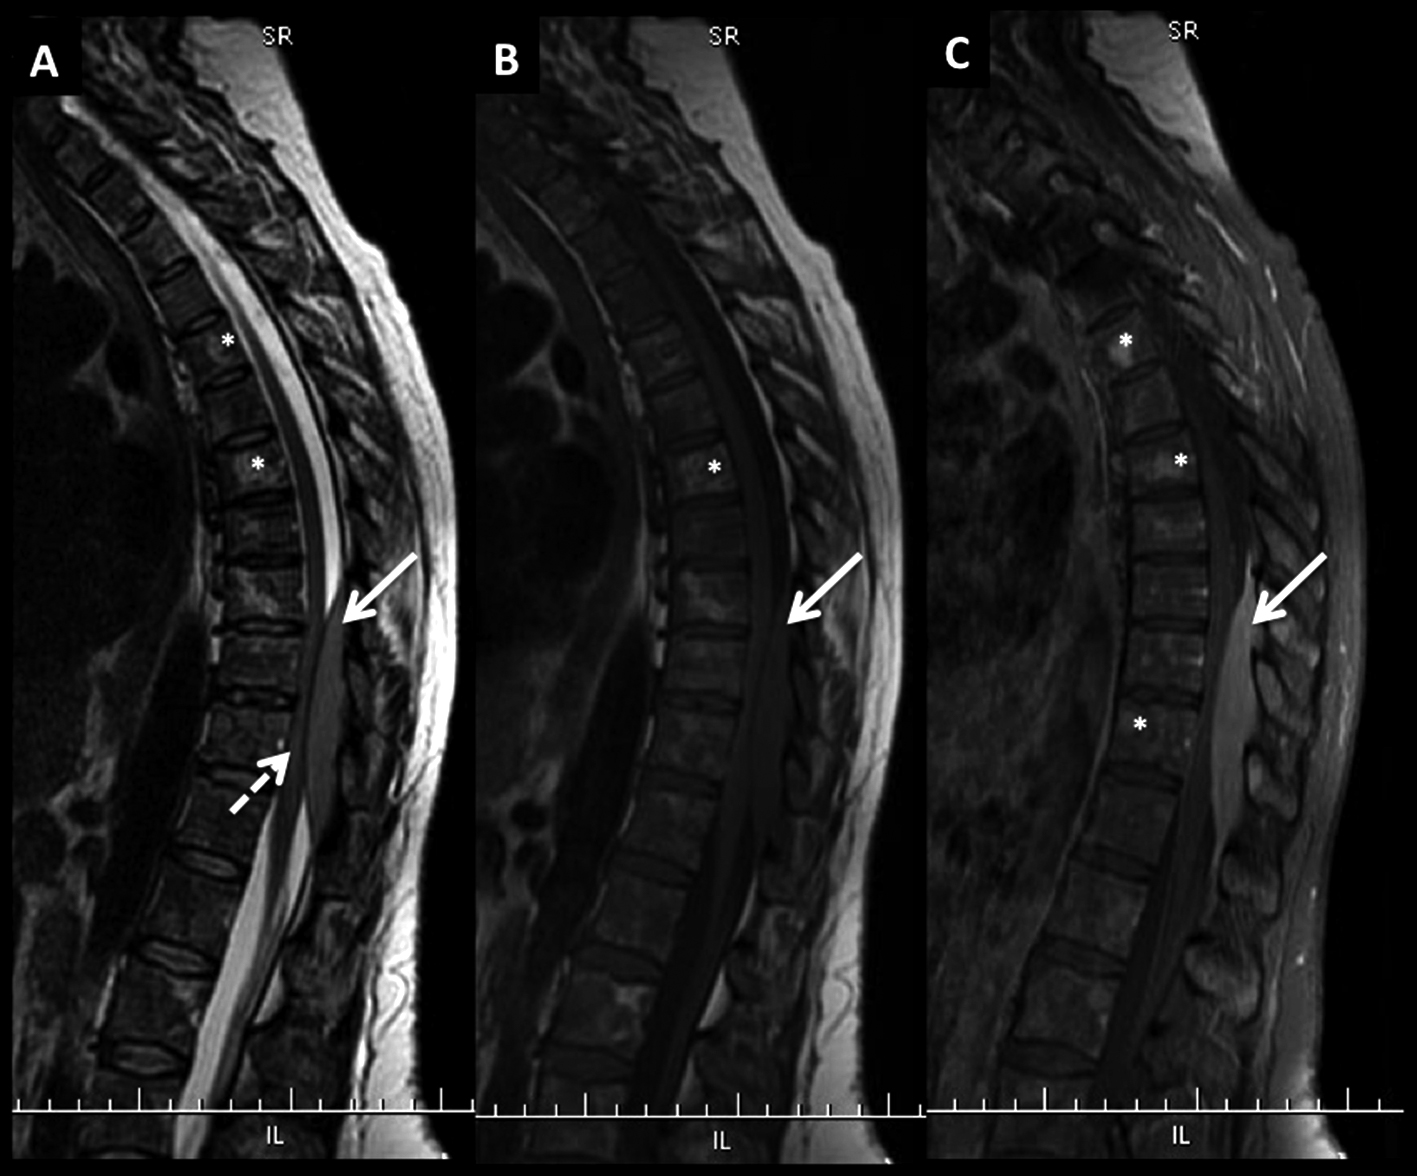

LNH, lesiones óseas múltiples y masa intrarraquídea extradural, compromiso secundario.

Paciente con diagnóstico de LNH sistémico y lesiones óseas múltiples (*) a nivel dorsal bajo y masa intrarraquídea extradural con compresión medular.

Las lesiones son de baja señal en T2 (A) y T1 (B) con edema óseo en STIR (C) y realce intenso, algo heterogéneo con el medio de contraste (D).

La masa intrarraquídea es sólida con intenso realce y que comprime el cordón medular. En secuencia T1 en fase (E) y fuera de fase (F) se observa el comportamiento habitual de las lesiones agresivas, con aumento de señal en el pasaje de una fase a la otra. En difusión b1000 (G) y mapa de ADC (H) las lesiones son de alta y baja señal respectivamente, un elemento habitual en lesiones agresivas.